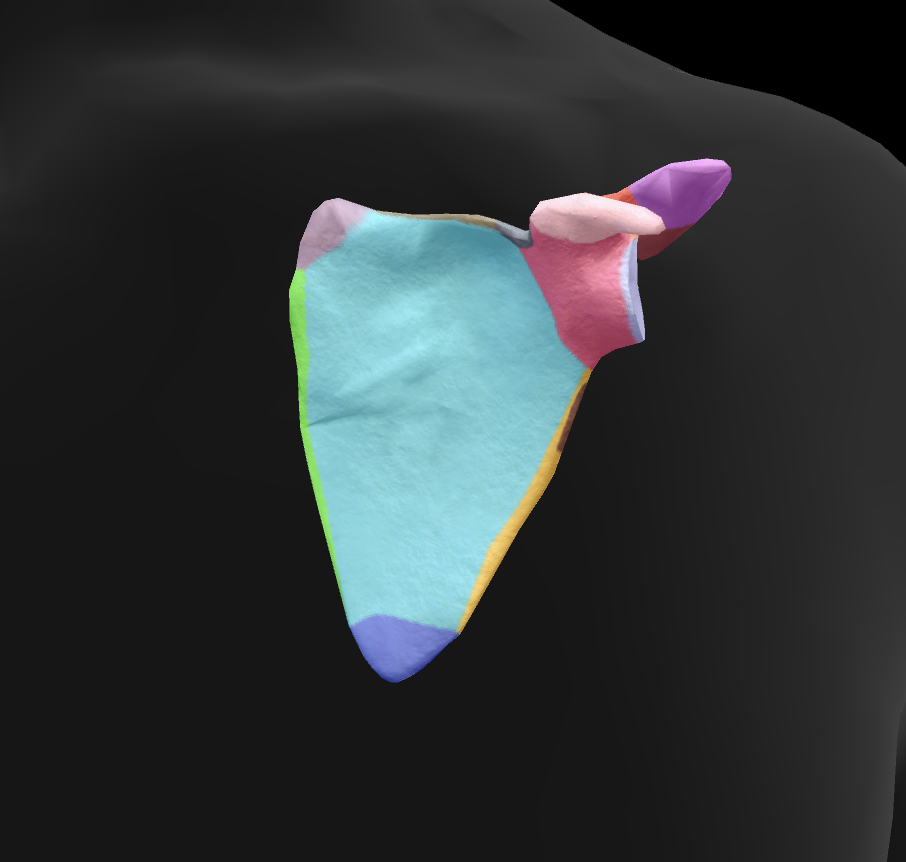

scapula

What is this boney landmark?

spine of scapula

What is this boney landmark?

supraspinous fossa

What is this boney landmark?

infraspinous fossa

What is this boney landmark?

acromion process

What is this boney landmark?

superior angle

What is this boney landmark?

inferior angle

What is this boney landmark?

lateral border

What is this boney landmark?

medial border

What is this boney landmark?

subscapular fossa

What is this boney landmark?

spinoglenoid notch

What is this boney landmark?

glenoid fossa

What is this boney landmark?

supraglenoid tubercle

What is this boney landmark?

infraglenoid tubercle

What is this boney landmark?

coracoid process